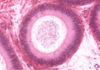

Pituitary - remnants of Rathke’s pouch

At pars intermedia, the circles are remnants of Rathke’s pouch

Pituitary - Pars intermedia

Pars intermedia: remnants of Rathke’s pouch